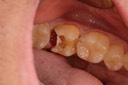

Kyle Chock #14 prep